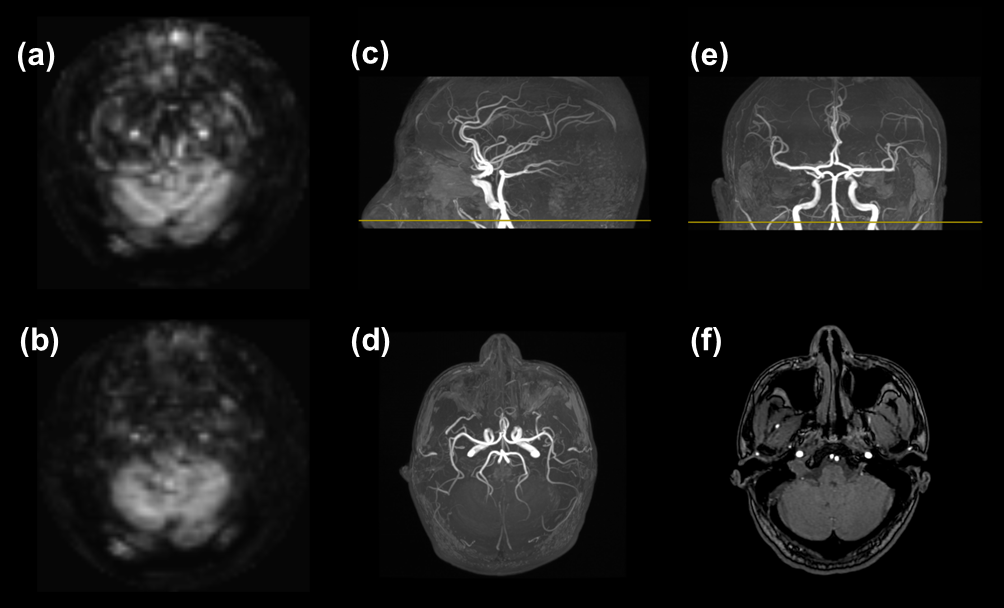

Figure 3. Perfusion images under the two ASL sequence conditions in reference with TOF angiography images for signal identification. A slice of perfusion images shows evident circular artifacts when the inferior saturation pulses are switched off (a), while the artifacts are virtually completely eliminated with the pulses switched on (b). Maximum intensity projection (MIP) of TOF in sagittal (c), axial (d), and coronal (e) planes, and axial pristine TOF image (f) were utilized to pinpoint the origin of artifact signals.

There were particularly distinct differences between ASL perfusion images with and without the inferior saturation for one of the four healthy volunteers. When no inferior saturation pulses were applied, artifacts in the forms of two bright spots and corresponding concentric rings could be evidently identified, especially in the inferior slices covering the cerebellum (Figure 2a). These artifacts were largely eliminated while the pulses were switched on in a following scan (Figure 2b). The artifacts can be more easily discerned by subtracting Fig. 1b from Fig 1a, as exhibited in Figure 1(c), where it’s distinct that the artifacts contaminate quite a few central slices as well. With a TOF angiography scan, we were able to directly attribute the bright spots to two large carotid arteries with inflowing blood (Figure 3). However, for the other three volunteers, such kind of artifacts was not observed with and without the incorporation of these saturation pulses. One such example is shown in Figure 4 where no swirls/circles could be discerned even in the subtraction image. The above scans were repeated 3-5 times for each of the volunteers and consistent results were obtained.